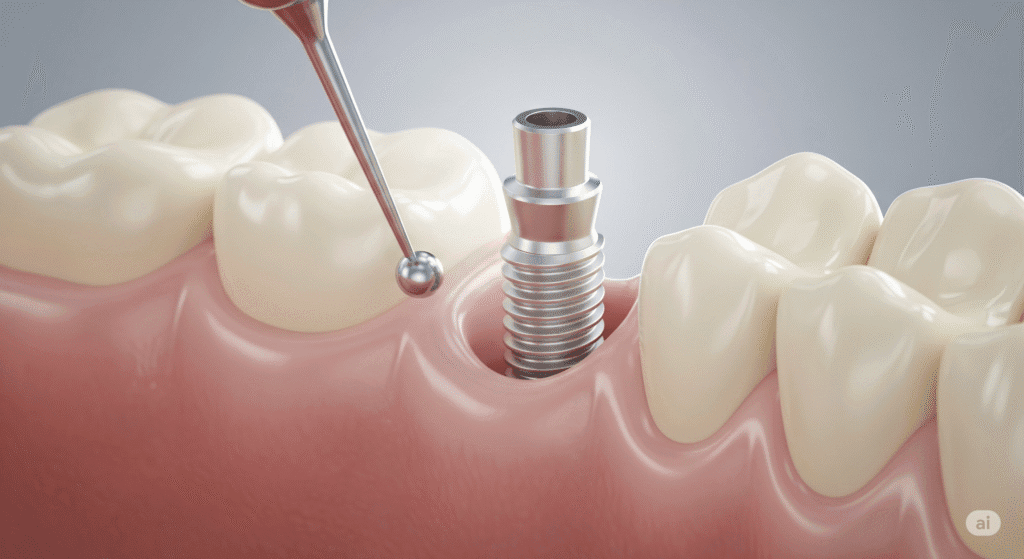

একটি আত্মবিশ্বাসপূর্ণ হাসি আপনার জীবন বদলে দিতে পারে। কিন্তু যদি দাঁতের অভাব আপনাকে পিছনে টানে? তাহলে, ডেন্টাল ইমপ্ল্যান্ট এর মাধ্যমে আপনার হারিয়ে যাওয়া হাসিকে ফিরে পান। ডেন্টাল ইমপ্লান্ট হল একটি স্থায়ী এবং প্রাকৃতিক সমাধান যা হারিয়ে যাওয়া দাঁত প্রতিস্থাপনের জন্য ব্যবহৃত হয়। ডাঃ অনুরাধা বোস ডেন্টাল ক্লিনিকে, আমরা আপনাকে আরামদায়ক,দীর্ঘস্থায়ীএবং উন্নত ডেন্টাল ইমপ্লান্ট চিকিৎসা প্রদান […]